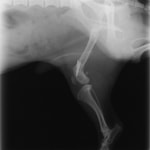

症例3:キルシュナーワイヤーのピンニングによる整復

ペルシャ猫 11ヶ月齢 雄

他院にて左大腿骨遠位の成長板骨折(salter-harrisⅠ型)が認められており、治療相談を目的として来院。当院にて、キルシュナーワイヤーを用いたピンニングにより骨折部位の整復を行いました。術後の経過は良好で、現在も経過観察中です。

術後レントゲン